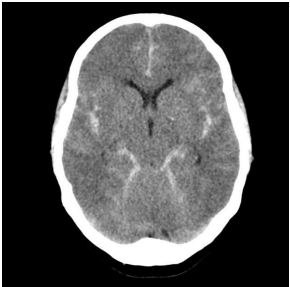

Uma paciente de 23 anos trazida inconsciente, sem história de trauma, dá entrada na sala de emergência e realiza essa tomografia. Qual seria uma possível causa para a principal alteração tomográfica?